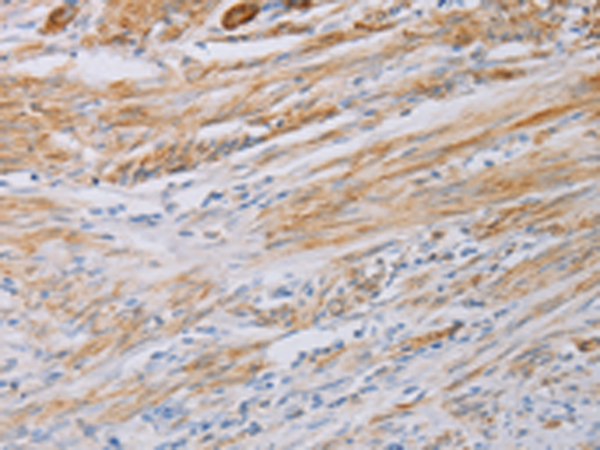

分类: 科研抗体货号: P07472别名: LC17; ESMLC; LC17A; LC17B; MLC-3; MLC1SM; MLC3NM; MLC3SM; LC17-GI; LC17-NM应用: WB,IHC反应种属: Human, Mouse, Rat